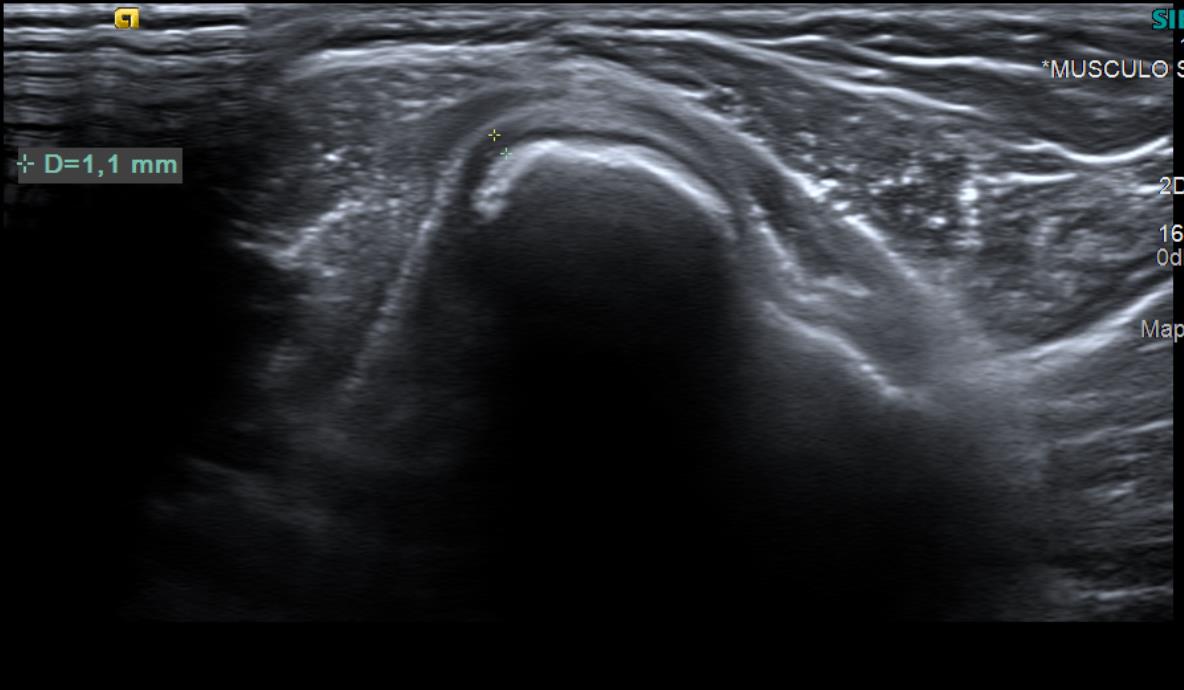

Con el objetivo de no irradiar al escolar, se decide realizar una ecografía desde el centro de salud, para poder obtener una mayor aproximación diagnóstica.

Ecografía: La tumoración referida corresponde a una excrecencia ósea con ribete hipoecoico circunante de 1 mm de espesor, sugestiva de lesión osteocondral.

Tras visualizar alteración en la ecografía del centro de salud, se deriva a radiología para realizar ecografía reglada y completar estudio con radiografía, así como realizar derivación para valoración por parte de Traumatología del Hospital Santa Lucía.

Gracias a la ecografía de Atención Primaria, se ha podido llegar al diagnóstico de manera precoz así como acortar los tiempos de espera.